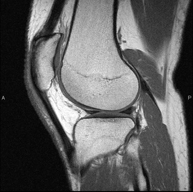

- Knee MRI

Examination to study joint injuries, such as meniscal tears and cruciate ligament tears (only detectable through this test), chondropathy or cartilage wear, and a multitude of other disorders resulting from sports activities and degenerative changes (osteoarthritis). It lasts approximately 18 minutes. It is a radiation-free procedure.